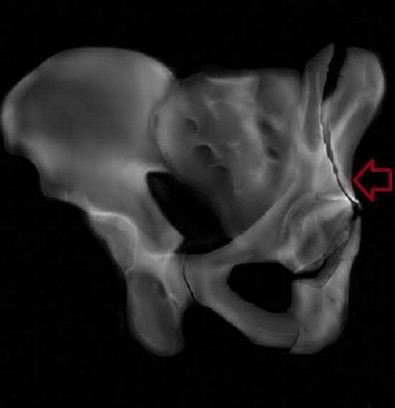

A poly-trauma patient presents hemodynamically unstable with an anteroposterior compression (APC-III) pelvic ring injury. A circumferential pelvic binder is requested to reduce pelvic volume and control hemorrhage. To be anatomically effective, the binder must be centered precisely over which of the following landmarks?

Correct Answer: Greater trochanters

Explanation:

For optimal mechanical advantage and effective reduction of an 'open book' pelvic fracture (APC type), a pelvic binder must be applied directly over the greater trochanters of the femurs. Applying it higher, such as over the iliac crests, is a common error that fails to adequately close the pelvic ring and can paradoxically open the true pelvis.